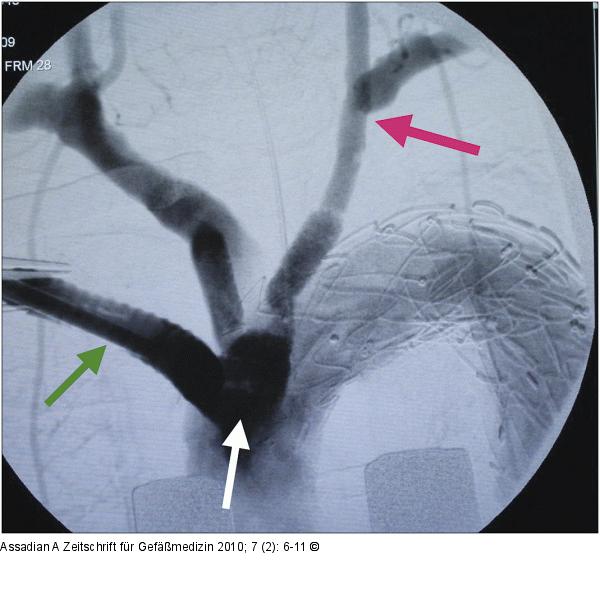

Abbildung 15: Abschlussangiographie Intraoperative Abschlussangiographie nach Stenteinbringung (Conduit über den der thorakale Stentgraft retrograd eingeführt wurde, grüner Pfeil; Subclaviatransposition roter Pfeil; Bypass auf Truncus brachiocephalicus und Art. carotis communis links, weißer Pfeil). |

Abbildung 15: Abschlussangiographie

Intraoperative Abschlussangiographie nach Stenteinbringung (Conduit über den der thorakale Stentgraft retrograd eingeführt wurde, grüner Pfeil; Subclaviatransposition roter Pfeil; Bypass auf Truncus brachiocephalicus und Art. carotis communis links, weißer Pfeil). |